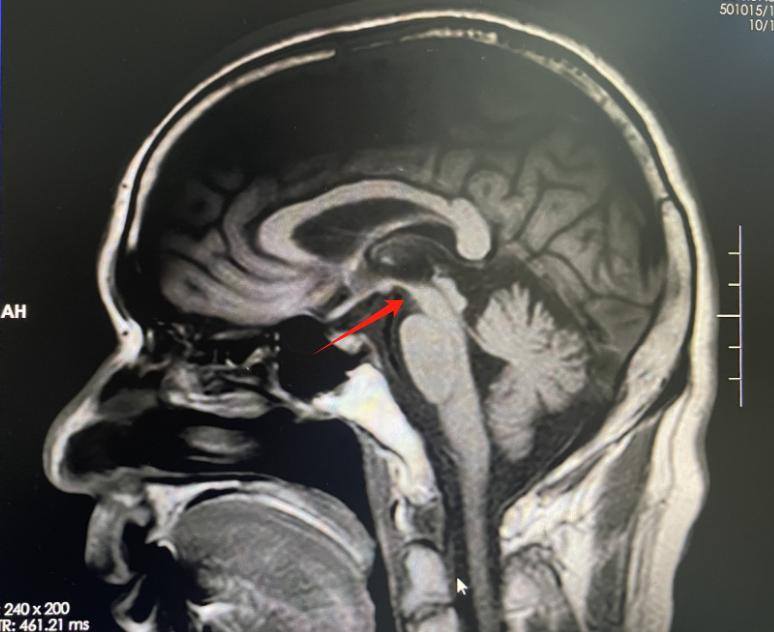

该院神经内一科副主任匡祖颖仔细询问患者病史,结合临床指征及磁共振成像提示中脑萎缩呈“蜂鸟征”,最终诊断为进行性核上性麻痹(PSP)。

▲MRI提示中脑萎缩,“蜂鸟征”

“患者以行动缓慢、姿势不稳起病,陆续出现眼球运动困难、肢体僵硬及情绪不稳定等症状,是典型的PSP。”匡祖颖介绍,PSP临床症状主要包括垂直性核上性凝视麻痹、姿势不稳易摔跤、运动和认知功能障碍,影像学上则表现出特征性的“蜂鸟征”。